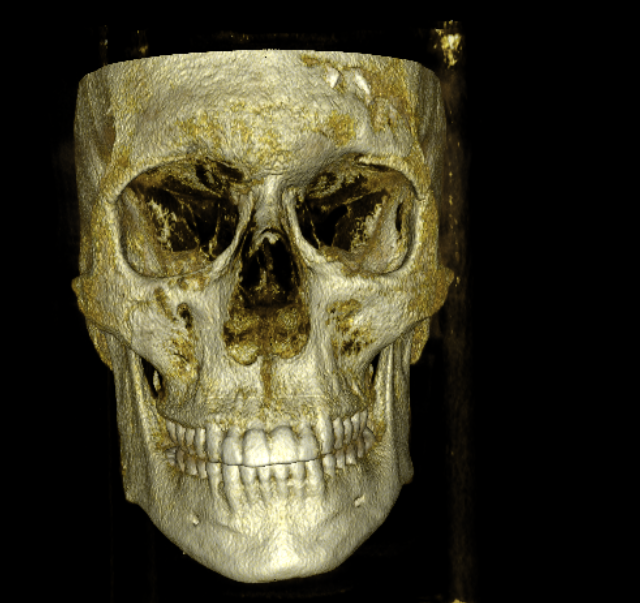

CBCT RENDERS

All attached. Frontal bone, left lateral, right lateral, soft tissue overlays, volume renders at different thresholds. The full skull, nothing hidden, nothing frauded with angles. You can see every problem I just described for yourself.

CBCT RENDERS

All attached. Frontal bone, left lateral, right lateral, soft tissue overlays, volume renders at different thresholds. The full skull, nothing hidden, nothing frauded with angles. You can see every problem I just described for yourself.